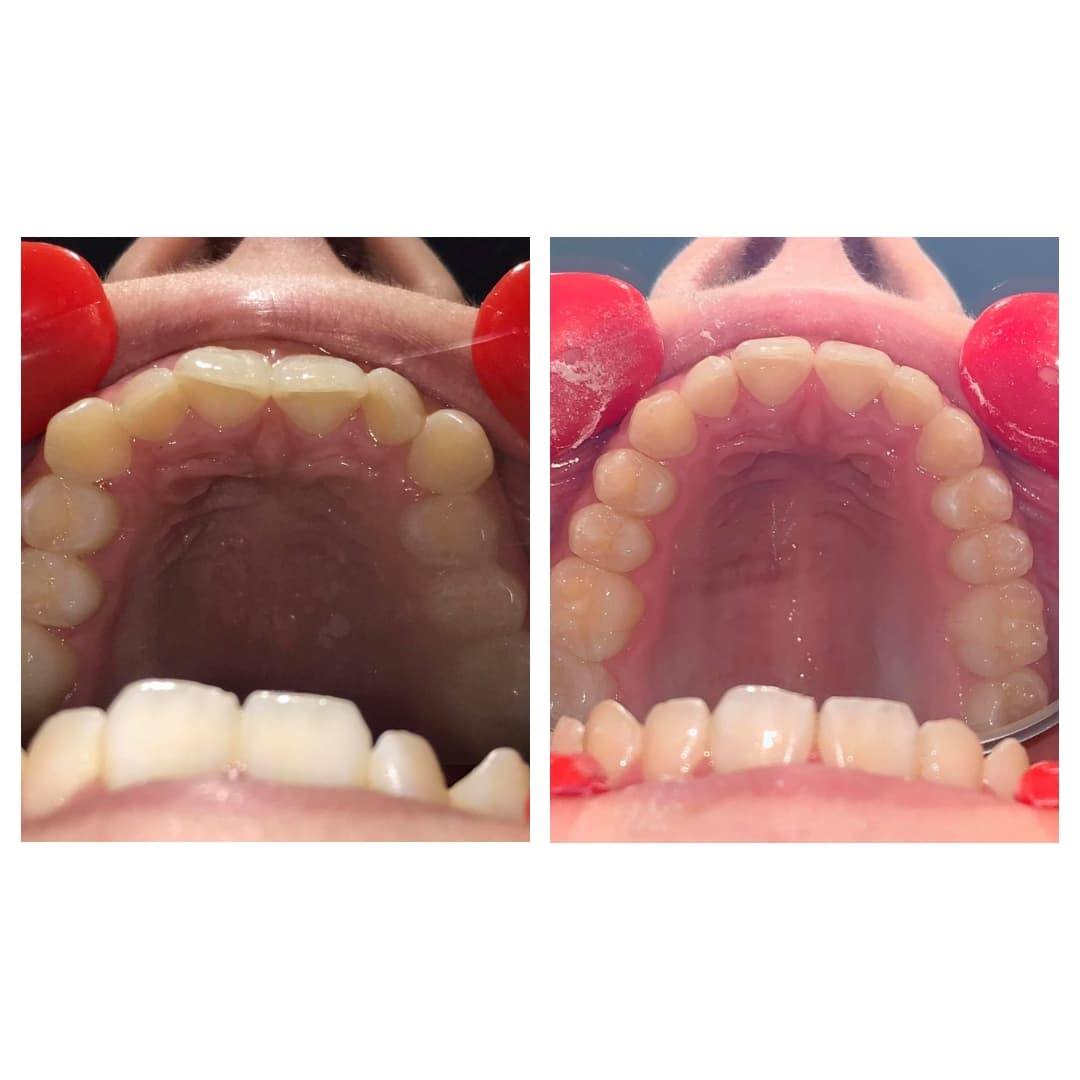

Pacjentka zgłosiła się do Kliniki Proste Zęby w maju 2019 roku, zadrutowana i załamana. Przyjechała do Warszawy z innego miasta, gdzie w gabinecie ortodontycznym otrzymała plan leczenia na 2,5 roku i założono jej klasyczny aparat z metalowymi zamkami i łukiem podniebiennym. Młoda, piękna dziewczyna jak usłyszała, że te druty i zamki ma nosić 2,5 roku to psychicznie była wyczerpana. Przed Julką matura, egzaminy, studniówka, szkoła wyższa. Julka nie była w stanie o niczym innym myśleć tylko o tym jak strasznie będzie na tych wszystkich wydarzeniach wyglądać! Rodzice szukali pomocy. Mama Julii znalazła Klinikę Proste Zęby w Internecie i przyjechali na wizytę START-UP dowiedzieć się czy jest możliwe zdjęcie tego aparatu i założenie Invisalign®. Po przeprowadzeniu diagnostyki, wykonaniu skanu komputerowego rodzice zdecydowali się w naszej klinice podjąć leczenia Julki. Zdjęliśmy druty i zamki, zdjęliśmy łuk podniebienny. Julka była przeszczęśliwa. Za około miesiąc w czerwcu otrzymała swoje nakładki Invisalign® i plan leczenia na 6 miesięcy! W grudniu 2019 roku, po przeprowadzonym leczeniu ortodontycznym, dokonano odbudowy protetycznej niewykształconych dwójek i Julka jest gotowa z nowym uśmiechem wejść w Nowy Rok pełen wyzwań maturalnych.